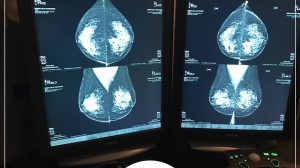

O raio-x é uma das ferramentas utilizadas para diagnosticar uma série de doenças, alterações ósseas e avaliar lesões. Com o avanço da tecnologia, o exame agora é mais rápido, prático e apresenta melhor resolução, fundamental para identificar possíveis problemas.

A Clínica Imax possui equipamentos de Raios-X Digital de última geração que permitem o aumento da qualidade dos exames radiológicos e garantem um nível de exposição à radiação muito menor.